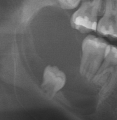

Figure 3. Elderly patient with previously unerupted tooth #17 presents with periodontal disease and bone loss which has also affected the second molar.

• Prevent gum disease. Periodontal disease can begin with the third molars and spread to other teeth. Always probe wisdom teeth, even distal to second molars on unerupted ones, to assess for deep pocketing and bleeding.5